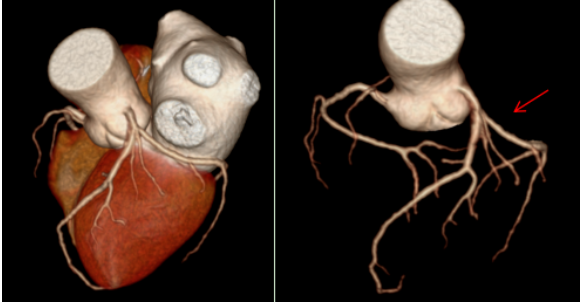

经过一系列检查,辽宁一脉阳光医学影像诊断中心医生通过冠状动脉CT血管成像(CCTA)发现,他的左冠状动脉前降支近端出现了中度狭窄,同时还伴有心肌桥的形成。这个结果,正是典型冠心病的表现。

在张大爷的病例中,CT影像清晰显示了他的左冠状动脉前降支近端有中度狭窄。前降支是冠状动脉中最重要的一支,负责左心室大部分血液供应。这里的狭窄,直接导致了他胸痛胸闷的症状。更特别的是,检查还发现了“心肌桥”,当心脏收缩时,心肌会压迫血管,进一步加重血流受限。这种结合了狭窄和心肌桥的情况,在老年患者中并不罕见,但也增加了诊断和治疗的复杂性。

从影像学角度看,CT冠状动脉成像是无创诊断的金标准之一。它通过三维重建技术,将冠状动脉的形态、狭窄位置和程度直观呈现出来。

在张大爷的检查中,医生利用宽体探测器CT获得了高质量的冠状动脉图像。图像清晰显示了狭窄的位置和程度,以及心肌桥的形态。这种技术的优势在于其高时间分辨率和空间分辨率,能够“冻结”心脏运动,避免运动伪影,从而提供诊断所需的精细解剖信息。此外,低剂量扫描技术的应用,还减少了辐射暴露,特别适合老年和体弱患者。